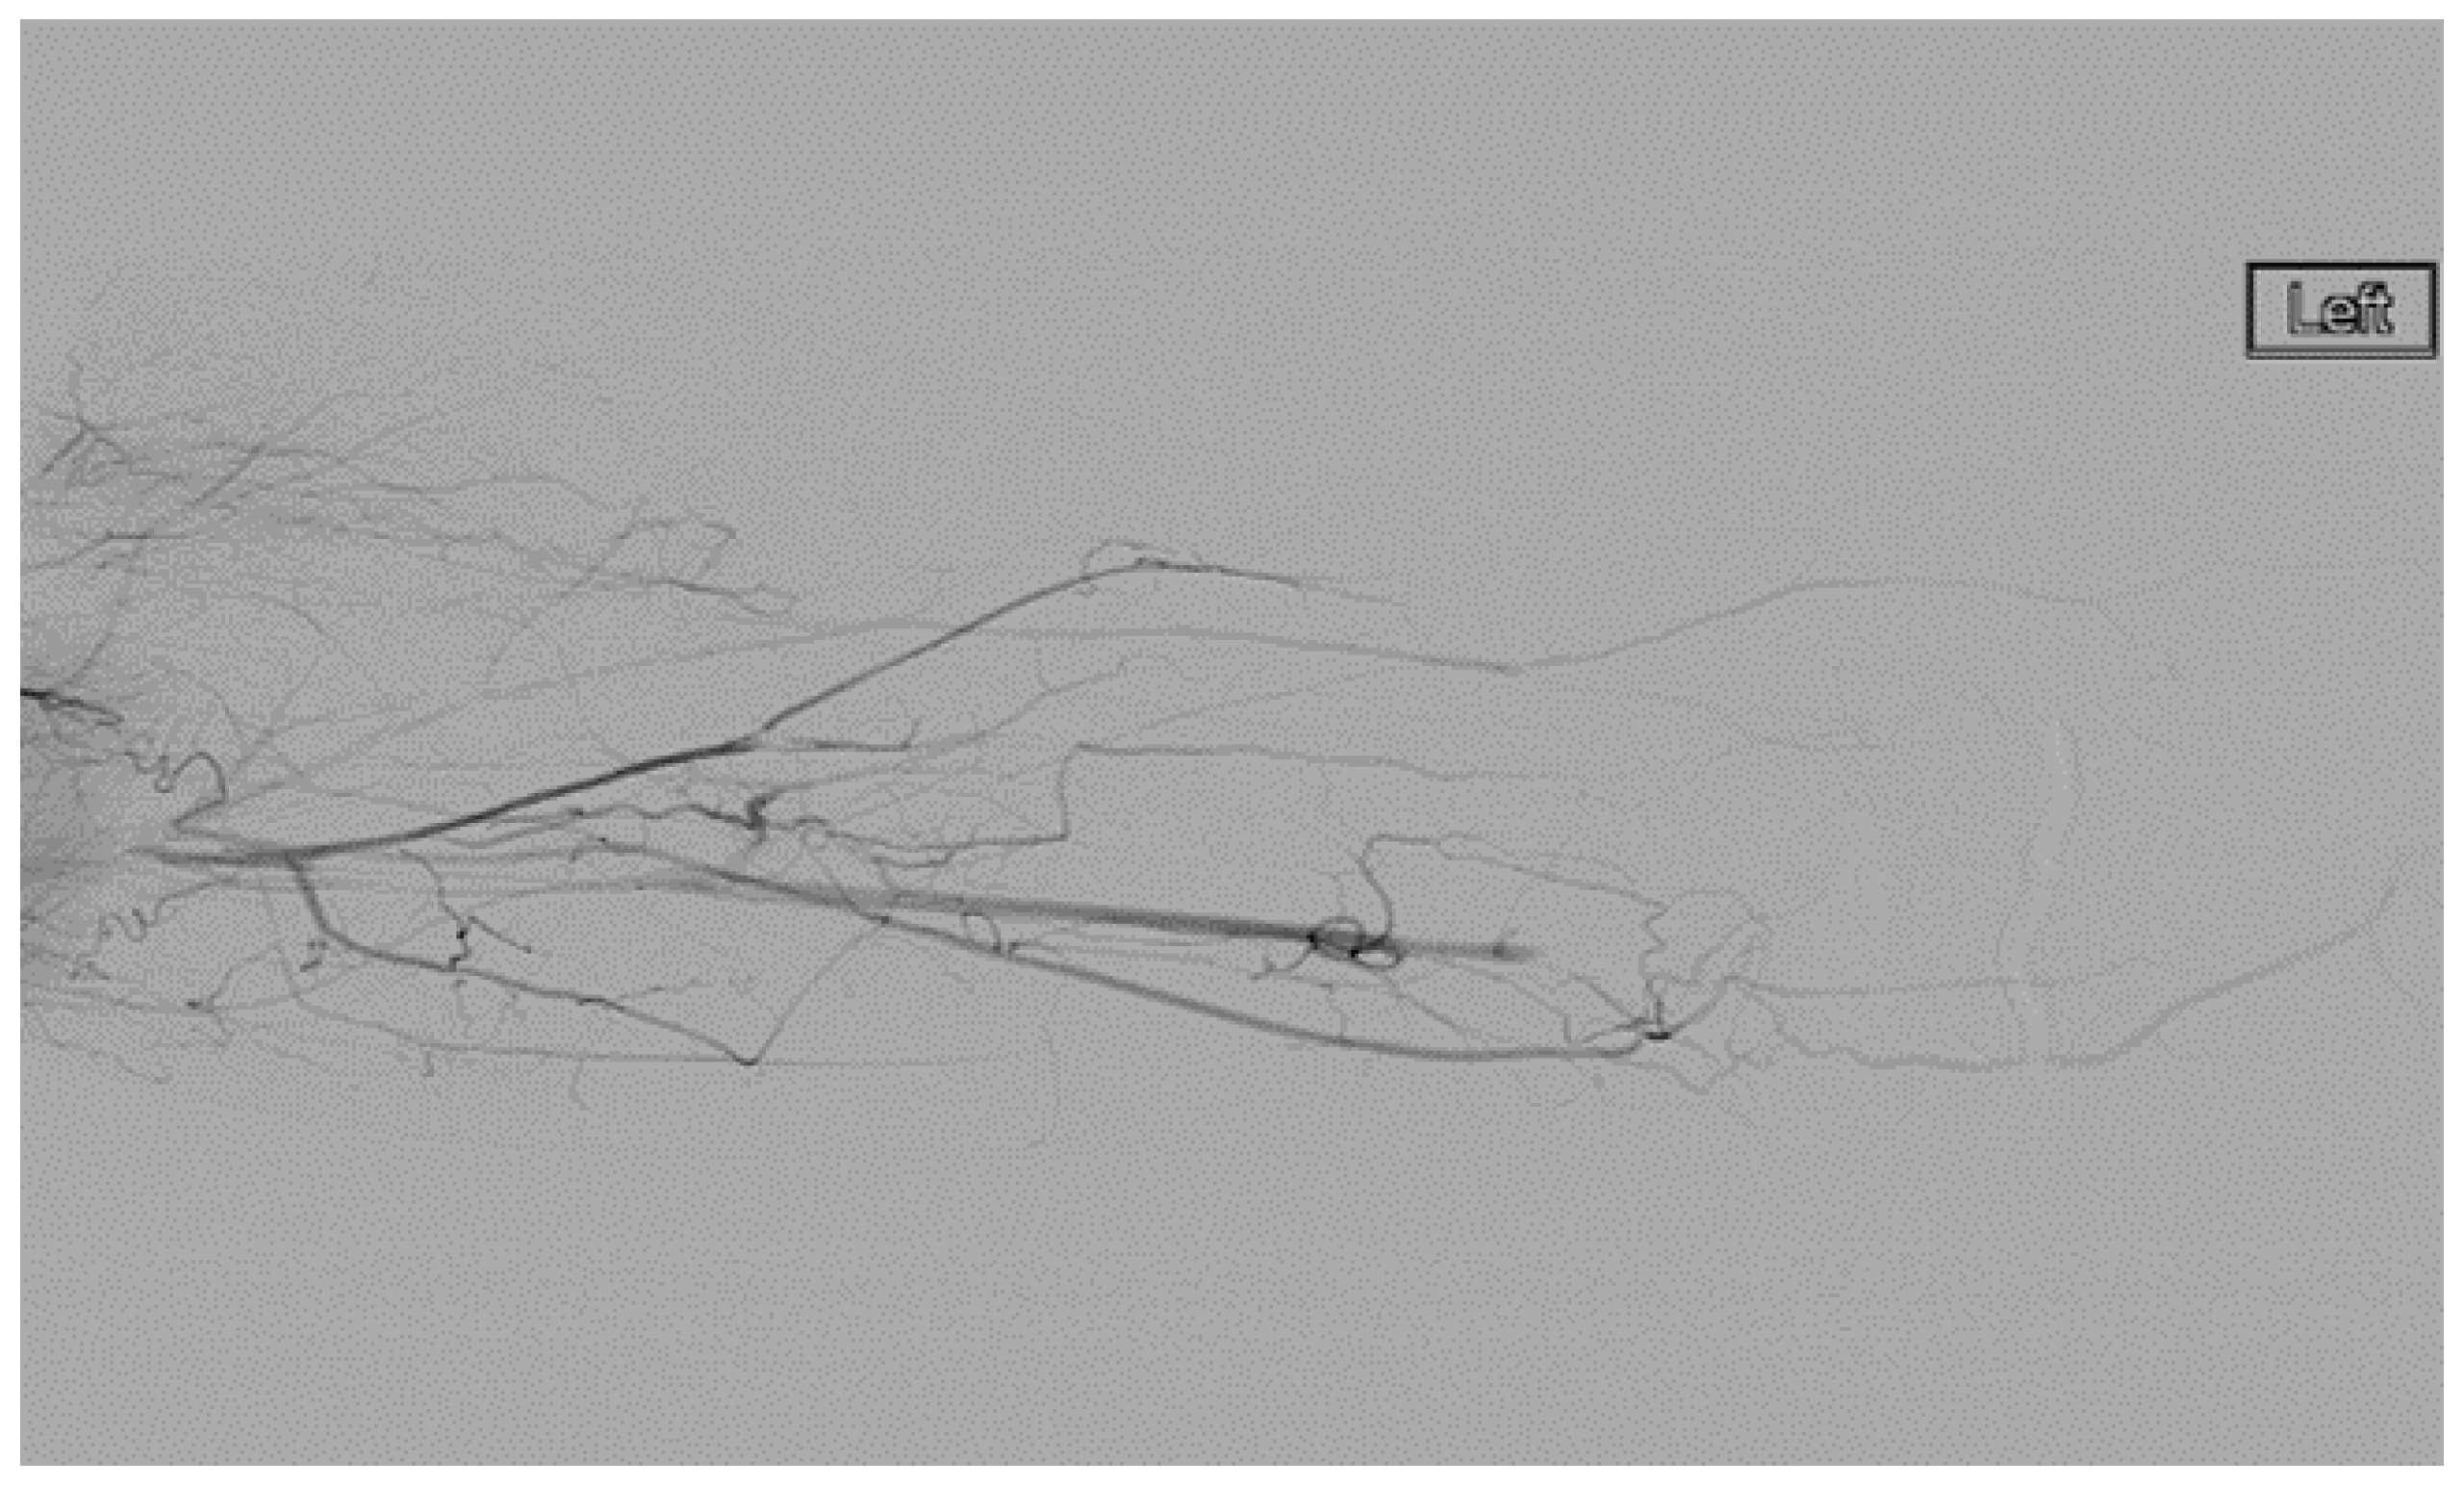

A heparin drip was then initiated, and she was taken to the catheterization lab for thrombolysis. This was carried out with Alteplase for 48 h as the patient had strong collaterals and was not in limb-threat (Figure 7, Figure 8, Figure 9, Figure 10 and Figure 11). However, her radial artery remained occluded. She was then taken to the operating room for thromboembolectomy of the left brachial and radial arteries (Figure 12). She was continued on anticoagulation post-operatively and was discharged.

Figure 9.

Distal left arm angiography in an ATOS patient demonstrating an occluded radial artery at the origin and ulnar artery at the mid-forearm.

Figure 10.

Angiography of the radial and ulnar arteries as well as the palmar arch and digital branches in an ATOS patient with a brachial thrombus.